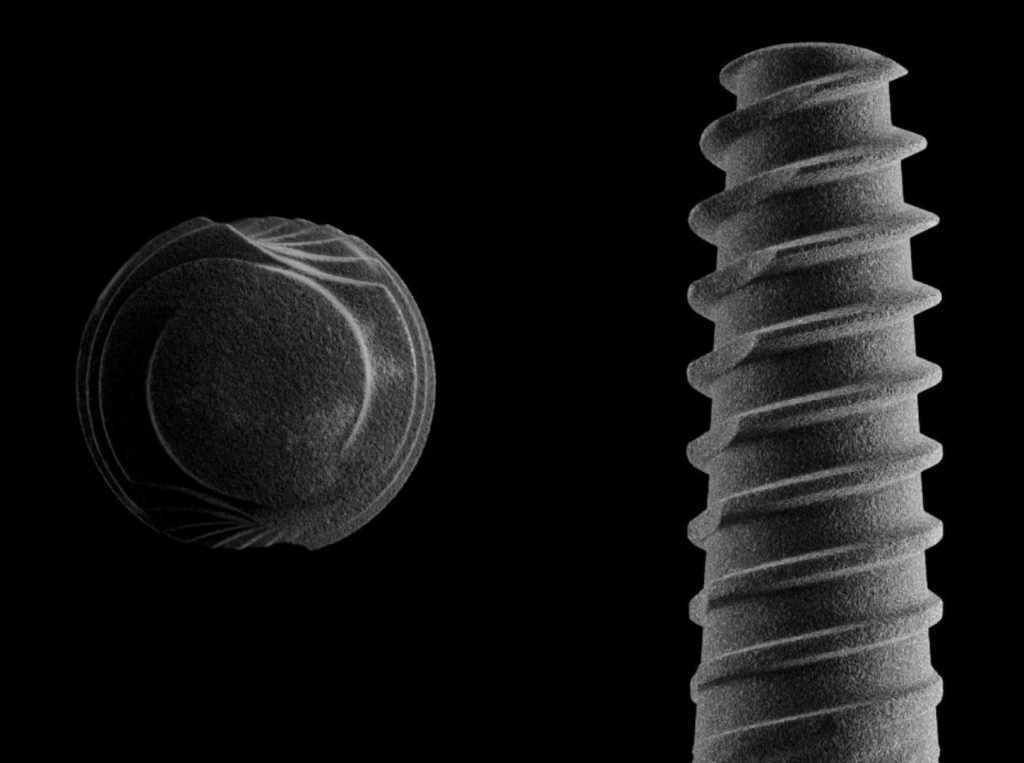

Cirugía Guiada por Ordenador

En nuestra clínica, ofrecemos cirugía guiada utilizando software 3D exacto, una técnica innovadora que nos permite planificar con precisión la colocación de los implantes y asegurar su correcta integración en el hueso maxilar o mandibular. De esta manera, podemos garantizar una colocación precisa, sin errores y con un mínimo de molestias para el paciente.

Según un estudio publicado en el Journal of Dental Research, la tasa de éxito de los implantes dentales a los 10 años es del 90-95%. Este estudio se realizó con una muestra de más de 2.600 implantes en 132 pacientes y se llevó a cabo en múltiples clínicas dentales en Europa. Además, el estudio encontró que la tasa de éxito de los implantes aumenta a medida que el tiempo de seguimiento se extiende, lo que sugiere que los implantes pueden durar mucho más que 10 años con un buen cuidado y mantenimiento adecuado.

Durante la cirugía, se utilizan guías quirúrgicas personalizadas basadas en esta planificación digital. Estas guías ayudan a posicionar el implante en el lugar exacto determinado en la planificación, asegurando que esté perfectamente alineado y rodeado de suficiente hueso, lo cual es crucial para su integración y estabilidad a largo plazo. Además, esta precisión garantiza que el implante esté en la posición óptima para recibir la prótesis dental, lo que mejora la funcionalidad y estética del resultado final.